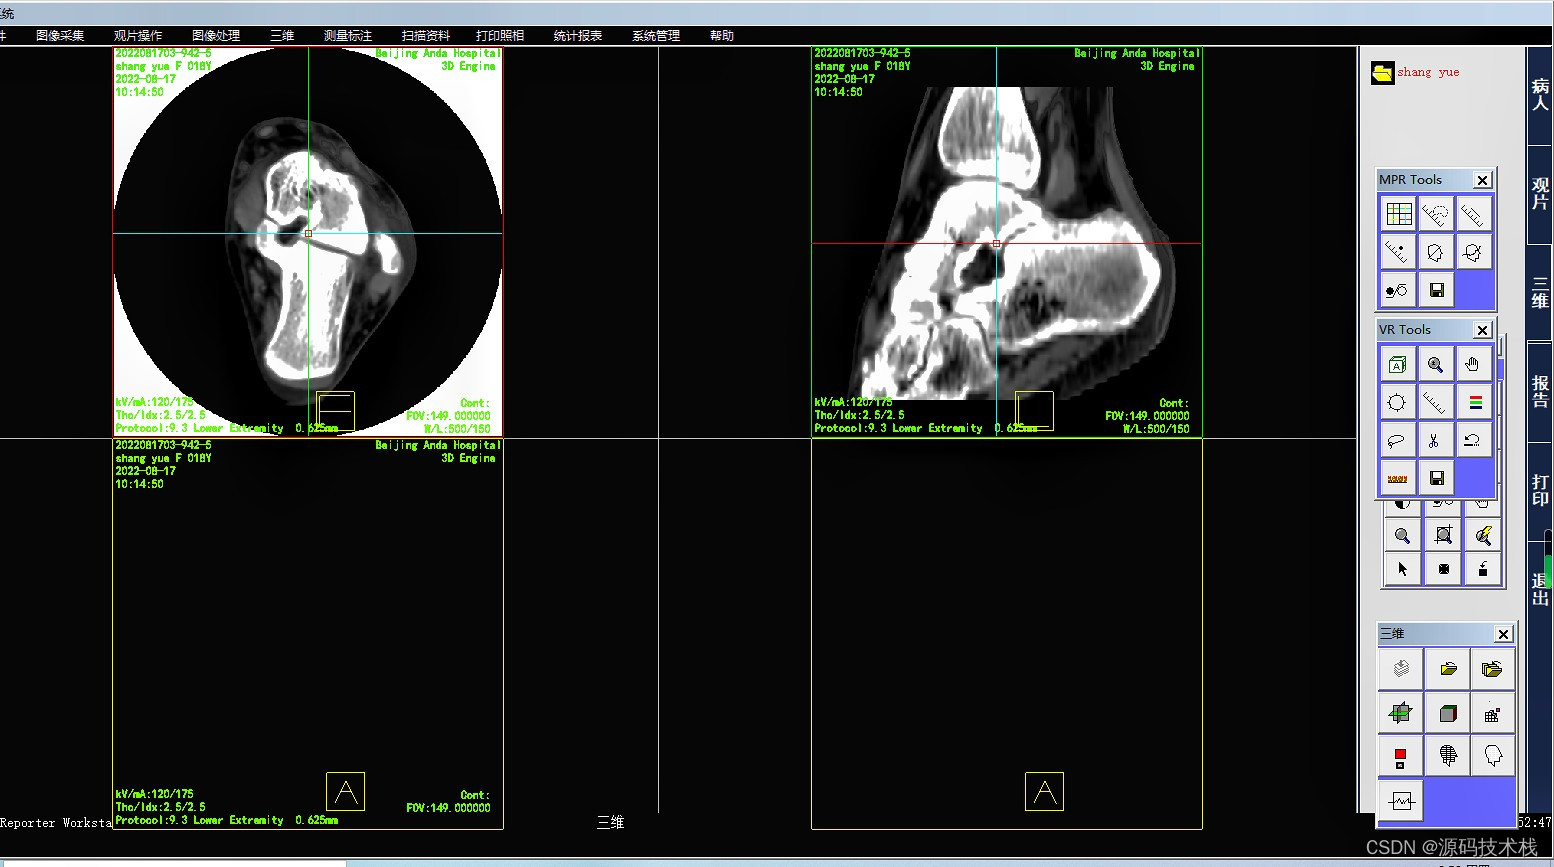

影像查阅

支持多屏和竖屏显示;支持动态影像电影方式回放、逐帧漫游和冻结;

支持同屏显示多幅影像,自定义显示矩阵;

支持检查模式、比较模式和打印模式的图像显示;

支持多屏显示同一患者的不同序列图像或不同患者的图像;

支持同屏分格显示患者不同体位和不同设备的影像;

图像后处理与重建

·MPR\CPR(三维多平面重建)

影像处理和测量功能

系统支持支持窗宽、窗位预设,连续调整窗口准位和直方图,图像均衡、图像平滑处理和边缘增强;

支持对比度调节、正负像旋转、影像黑白反转、影像水平和垂直翻转、灰阶转换和任意角度旋转等;

支持滤波、锐化、播放和彩色绘制等;

支持ROI值、长度、角度和面积等数据测量与计算;

支持数字减影、无级缩放和局部放大;

支持文字和图形标记;查询和保存DICOM头信息;

支持不同影像格式转存;

支持根据检查项目自动应用相应的预设窗宽、窗位。